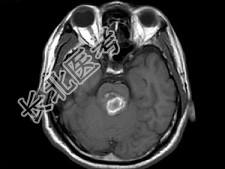

- 单项选择题男,42岁, 头晕视物旋转,面部麻木半月余, 根据所提供图像,最可能的诊断是 ( )

A、脑干动静脉血管畸形

B、脑干出血

C、脑干血管瘤

D、脑干胶质瘤并出血

E、脑干梗死